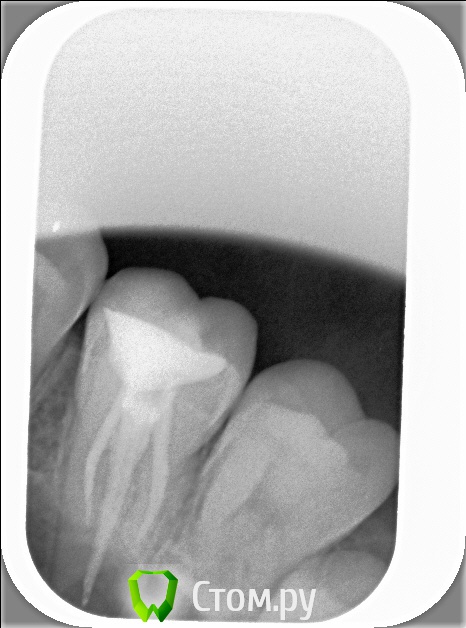

xSlon Опубликовано 13 августа, 2014 Поделиться Опубликовано 13 августа, 2014 Доброго времени суток!Прошу вашей помощи по сложному зубу, который не могут вылечить уже очень длительное время. Около 3х лет назад обнаружил, что при постукивании по 16му зубу(он был запломбирован совсем давно, не помню даже где и в каком году) появляется небольшая боль. Зуб не мешал, не доставлял беспокойств, но решив, что в таких случаях нужно действовать превентивно, пошел к стоматологу и рассказал о проблеме. Он посмотрел зуб(без вскрытия), сказал что никаких признаков боли не видит и считает что нужно удалять нерв. Поскольку зуб проблем не доставлял, я отказался.В течение этих трех лет состояние не ухудшалось, но я еще два раза ходил к разным стоматологам, описывал симптомы, они смотрели зуб, никаких признаков болезни не видели и советовали заниматься зубом когда он будет доставлять настоящие неудобства.В середине октября 2013 года ситуация ухудшилась, зуб начал периодически не сильно болеть, реагировать на холодное и горячее. В середине декабря ситуация сильно ухудшилась, зуб начал сильно болеть, сильно реагировать на холодное и горячее, сильно болеть даже при простом касании. Я обратился в стоматологию1 к врачу1, где мне вскрыли зуб, сказали что обнаружили под пломбой кариес, из-за кариеса произошло воспаление нервов и нужно удалять нервы в зубе. Боль была очень значительной, я не раздумывая согласился. Мне вскрыли зуб, поставили обезболивающее(или лекарство - точно не знаю), и сказали прийти через 7 дней, боль прошла. Через 7 дней мне обработали каналы и запломбировали Metapex'ом, сказали прийти в феврале(возможно еще удалили лекарство, точно не помню). В феврале мне за 1 посещение запломбировали постоянно каналы и за 2е посещение запломбировали зуб. К середине февраля лечение закончилось, жалоб не было. Единственное - удивляло что зуб, несмотря на удаление нервов, по старому реагирует на постукивание небольшой болью, но я не придал этому большого значения.Спустя 2 месяца, в середине апреля, остро заболел тот же самый зуб, с теми же симптомами - сильная боль, сильная реакция на холодное и горячее, сильная боль при касании. Врач1 был в отпуске, поэтому я пошел к Врачу2 в ту же самую Стоматологию1. Описал ситуацию, Врач2 посмотрела мою карточку, вскрыла зуб, осмотрела его, сказала что где-то должен быть 4й канал, но она не может его найти, сказала что вставила куда-то в зуб лекарство, сказала прийти через неделю.Боль утихла, пришел через неделю к тому же Врачу2, повторно вскрыли зуб, повторно поставили лекарство, но Врач2 сказала что 4го канала, который там должен быть, она не видит. Посоветовала обратиться к другому врачу, возможно, в другую стоматологию Через неделю, уже в начале мая, пришел повторно, запломбировали каналы Metapex'ом, поставили временную пломбу. По совету знакомых, в начале июня обратился к частному Врачу3, который специализируется на работе под микроскопом. Описал ей ситуацию, она вскрыла зуб, нашла четвертый канал, вставила туда лекарство, сказала прийти через неделю. Через неделю реакция зуба на слабые постукивания сохранилась, на приеме у Врача3 поставили более сильное лекарство(насколько я помню, с антибиотиком), прописала дополнительно в течении 5 дней пропить сильные антибиотики, сказала прийти через 10 дней. Через 10 дней, в конце июня, та же реакция зуба сохранилась. На приеме у Врача3 решили окончить лечение, потому как Врач3 на следующий день уходила в отпуск, а я, через несколько дней, уезжал в командировку. Перед отъездом пошел в Стоматологию1 к Врачу2, чтобы снять лекарство и временно запломбировать каналы и поставить временную пломбу. Врач2 сказала, что при вскрытии зуба она увидела 4й канал, попыталась определить длину канала с помощью прибора, используя самый тонкий инструмент(как я понял - это некая игла, подсоединенная к прибору, ее всовывают в канал, чем ближе кончик иглы к концу канала, тем сильнее он пищит), определить длину канала ей не удалось. Она предположила, что либо канал очень узкий, либо он изгибается, поэтому не удается дойти до конца канала.В командировке, в середине июля обновлял временную пломбу(от нее отвалился небольшой кусочек) в Стоматологии2, вкратце описал проблему Врачу4, он посоветовал использовать(дословно с листочка, который он мне дал) пломбировку материалом для к/к Forfenan Forident(резорцин-формалиновая паста). Сказал, что при таком методе, воспаленный нерв полностью обволакивается пастой, которая гермитизирует нерв, не давая разиваться воспалительному процессу. Сам воспаленный нерв остается, но организм, со временем, справляется с ним сам.Вернувшись из командировки, я пошел, по советам родственников, в Стоматологию3, к Врачу5. Описал ситуацию, сделал панорамный и прицельный снимки. Врач5, не вскрывая зуб, сказала что считает, что необходимо применить метод депофореза. Прошу вас, пожалуйста, посоветовать, каким образом вылечить этот зуб? Стоит ли попробовать резорцин-формалиновую пасту? Стоит ли делать метод депофореза? Возможно есть какие-то другие методы лечения? Прикладываю все снимки зуба из Стоматологии1Панорамный снимок из Стоматологии3, сделан 12 августа. https://yadi.sk/i/_hIqGP1IZaT4Y Ссылка на комментарий

xSlon Опубликовано 14 августа, 2014 Автор Поделиться Опубликовано 14 августа, 2014 Добавлен прицельный снимок 16го зуба от 12го августа. К сожалению, не нашел, как отредактировать первый пост. Ссылка на комментарий

Scrabble Опубликовано 31 августа, 2014 Поделиться Опубликовано 31 августа, 2014 Я вижу, что Вам запломбировали каналы термафилами-причём два носителя введены в дистальный, а не в мезиальный щёчный корень. В качестве силера(пасты) использовался форфенан? Если это так, то нужно всё распломбировать, полностью удалить форфенан-и ждать, пока стихнет симптоматика. Ссылка на комментарий

xSlon Опубликовано 8 сентября, 2014 Автор Поделиться Опубликовано 8 сентября, 2014 Позвонил Врачу3, проконсультировался с ней - она посчитала что ее вмешательство не нужно, имеет смысл сходить к Врачу2, просто поставить временную пломбу.Ходил 03.09.14 к Врачу2 в Стоматологию1 - сменили метапасту в небном, дистально- и медиально-щечном, медианно-небном поставили жидкость форадент, поставили временную пломбу СИЦ.Я вижу, что Вам запломбировали каналы термафилами-причём два носителя введены в дистальный, а не в мезиальный щёчный корень. В качестве силера(пасты) использовался форфенан? Если это так, то нужно всё распломбировать, полностью удалить форфенан-и ждать, пока стихнет симптоматика.Просмотрел всю карточку из Стоматологии1, слова форафен там не нашел. Скажите, пожалуйста, на каком снимке вы это увидели? Ссылка на комментарий